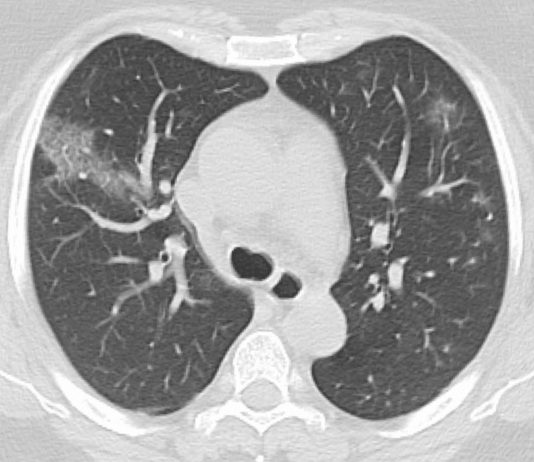

Uomo di 64 anni affetto da diabete mellito ed ipertensione. Da 3 giorni dispnea, tosse ed iperpiressia. Emocromo e procalcitonina nella norma. PCR elevata (13,44 mg/dL).

RX torace